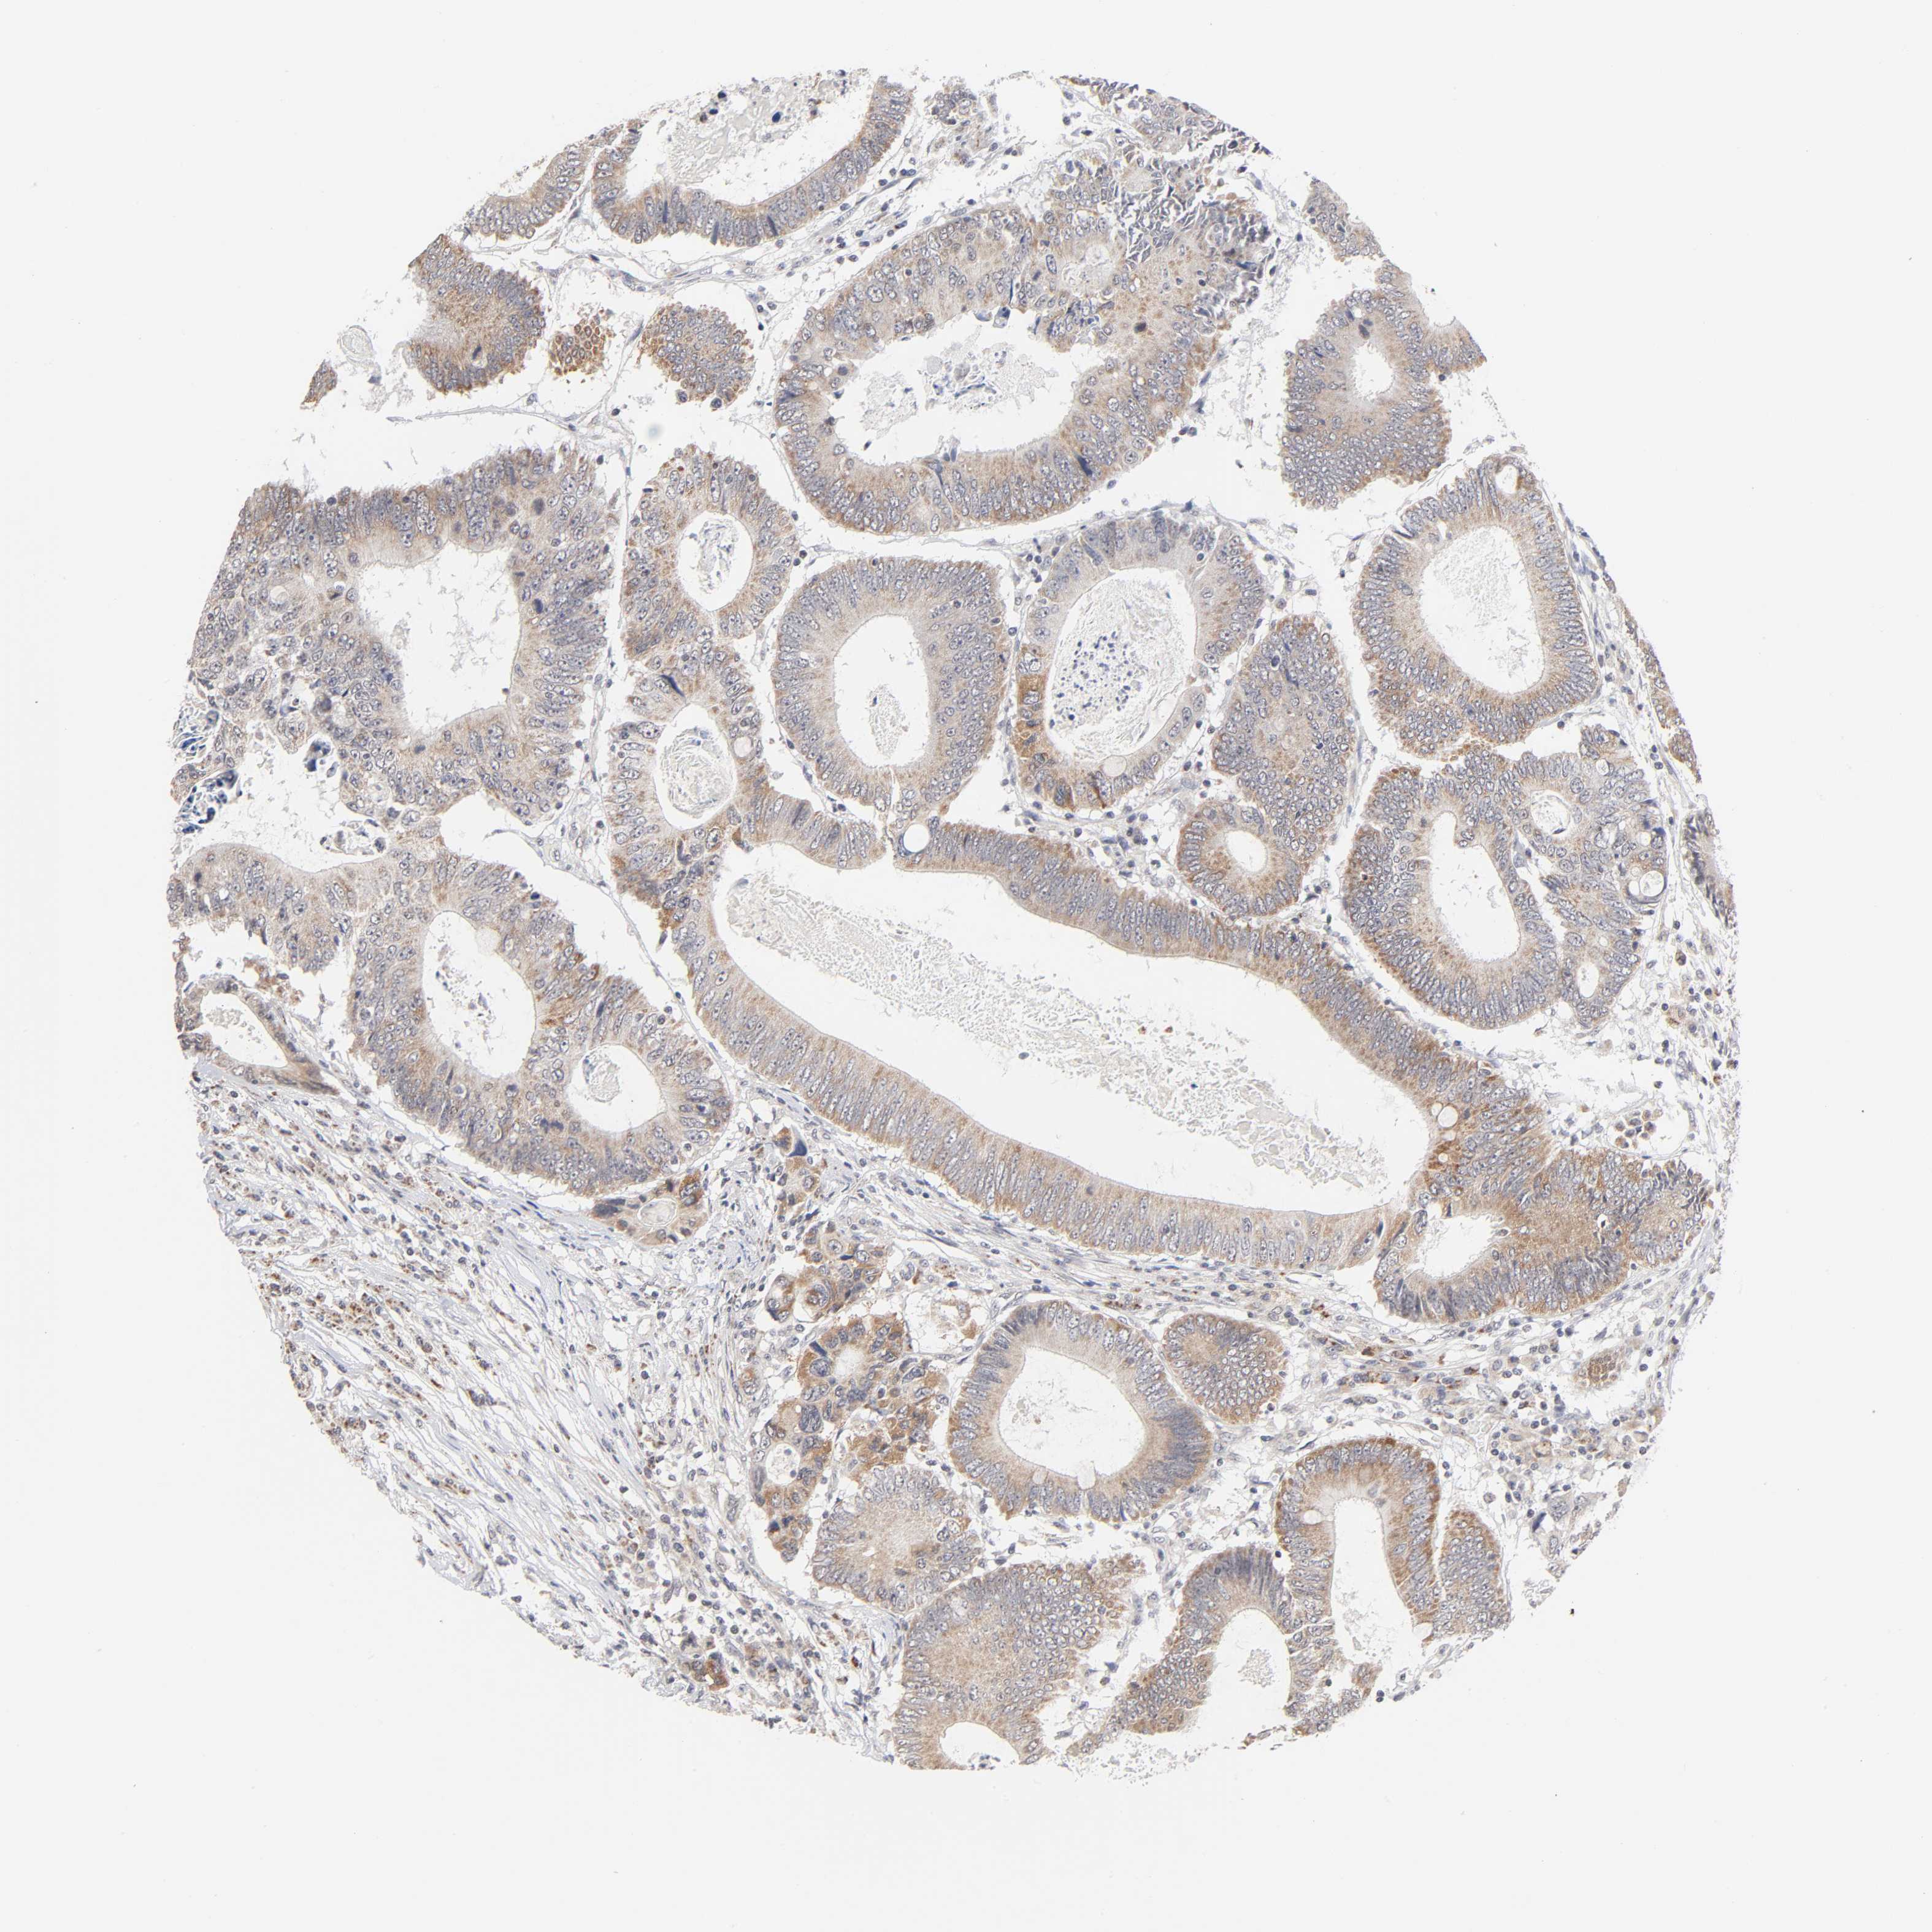

CANCER COLORECTAL CANCER Show tissue menu

ANTIBODIES

AND

VALIDATION